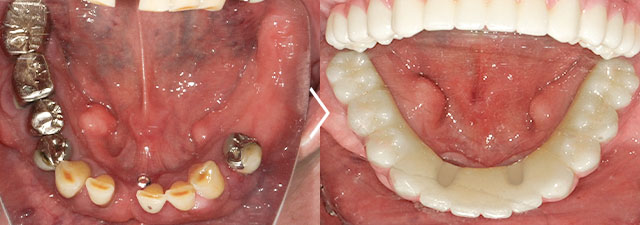

この患者様は上顎をすでにオールオン6で治療済みで、今回は下顎をオールオン6で治療しました。

オールオン6 セラミックタイプ ¥3,100,000(税抜)